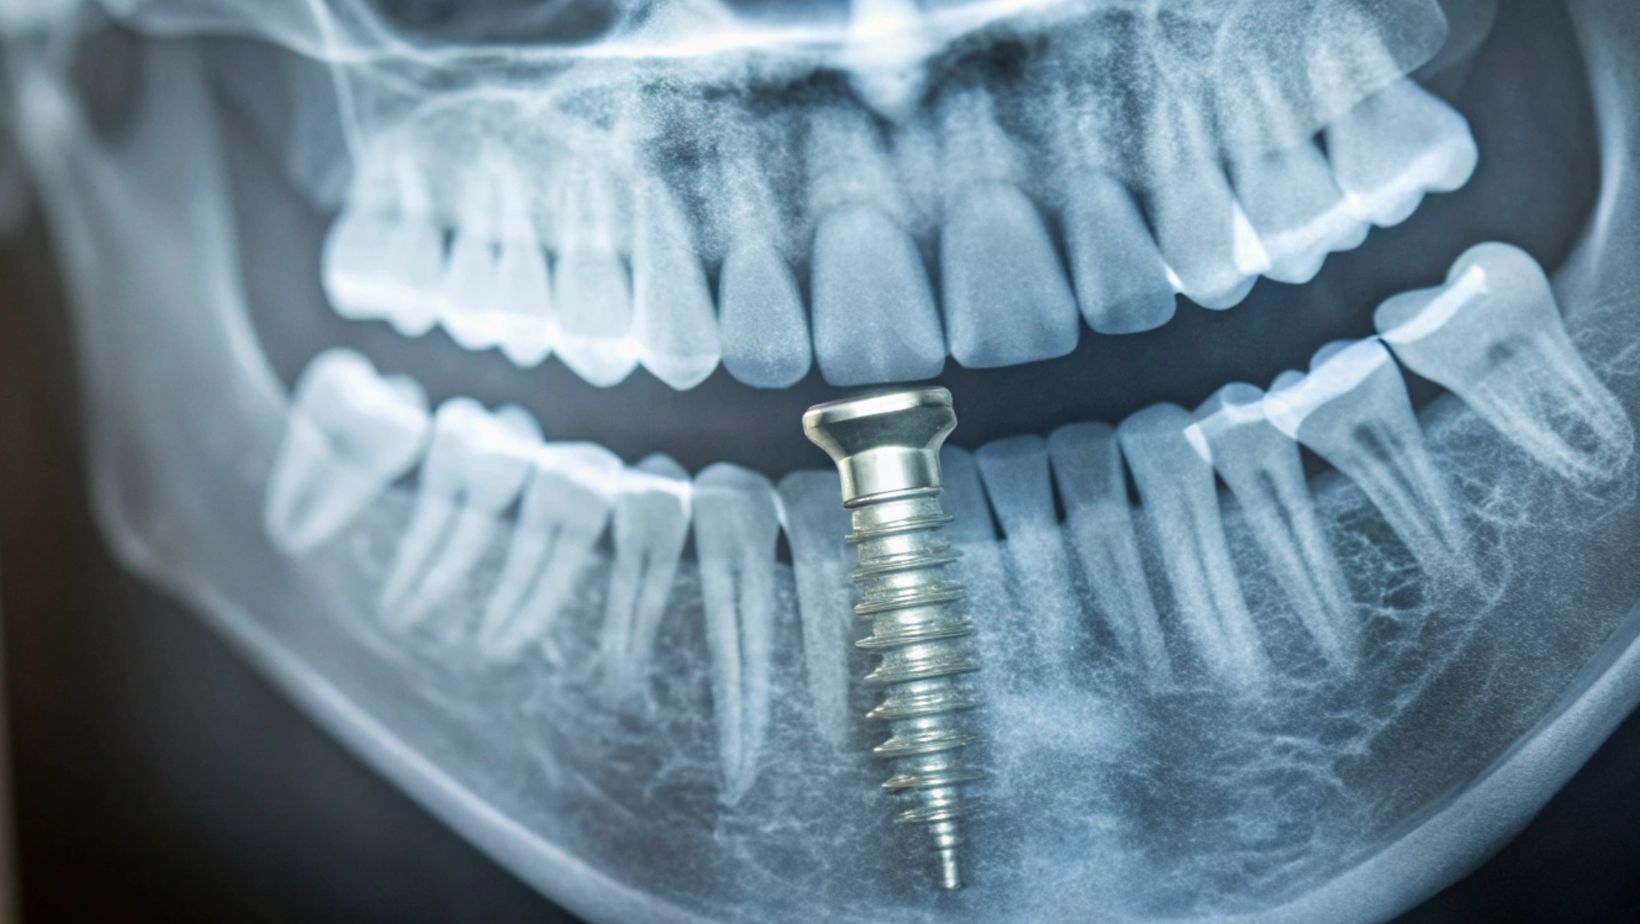

Pterygoid implants are long dental implants placed in the pterygoid region of your upper jaw. This area is near the back of your mouth, where the maxillary tuberosity meets the pterygoid process of the sphenoid bone.

This bone area is dense and strong, making it a good place for implants when your upper jawbone has lost volume. The implants anchor into the pterygoid plates, which are part of the sphenoid bone, allowing better stability without needing bone grafts or sinus lifts.

The placement of pterygoid implants starts with an assessment of your jaw anatomy using scans and exams. During surgery, your dentist will angle the implant to engage the strong pterygoid bone behind the jaw.